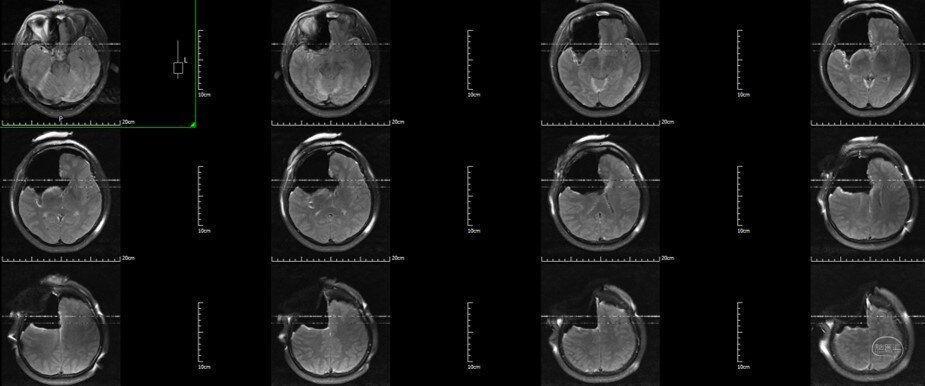

术中T2 Flair

术中T2

术前 VS 术中